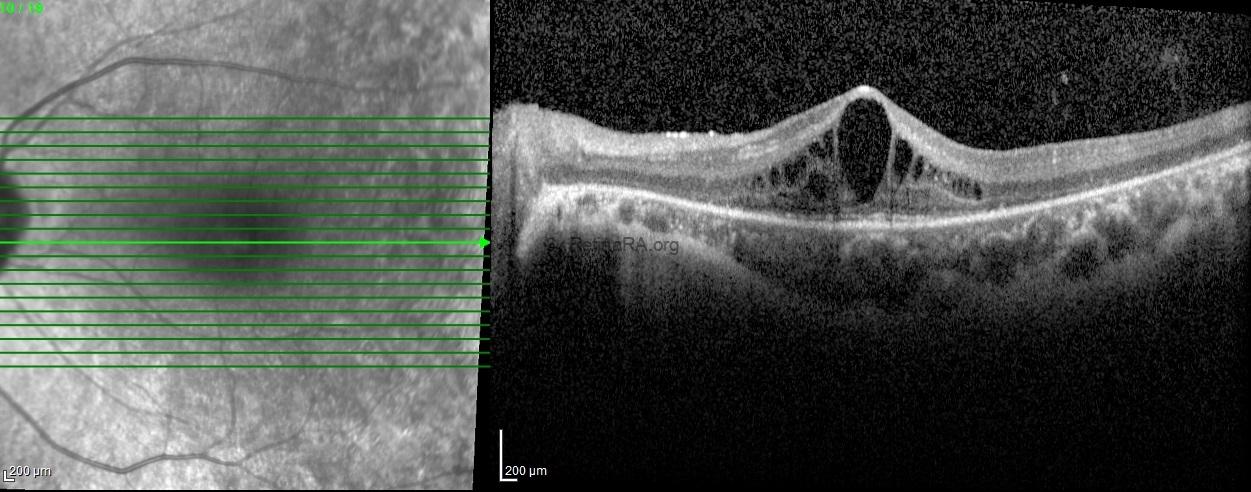

Optical coherence tomography scans revealed decreased thickness of the outer nuclear layer, along with loss of the external limiting membrane and ellipsoid zone in both eyes, sparing the fovea. Hyporeflective cystoid spaces were also observed in both eyes.

A clinical diagnosis of Usher syndrome was made based on the history (poor night vision and hearing impairment since childhood), clinical findings (peripheral vision loss, mid-peripheral bony spicules, and arteriolar attenuation), and investigative results (optical coherence tomography, electroretinography, and pure tone audiometry).

Usher syndrome is an autosomal recessive disorder combining congenital sensorineural hearing loss with progressive retinal degeneration (retinitis pigmentosa). Fundus findings typically include bone spicule pigmentation, arteriolar attenuation, and optic disc pallor. Optical coherence tomography often reveals thinning of the outer retinal layers with loss of the ellipsoid zone, sparing the fovea in early stages. Full-field electroretinography demonstrates markedly reduced or extinguished scotopic and photopic responses. Early recognition allows appropriate genetic counseling, auditory rehabilitation, and multidisciplinary management.